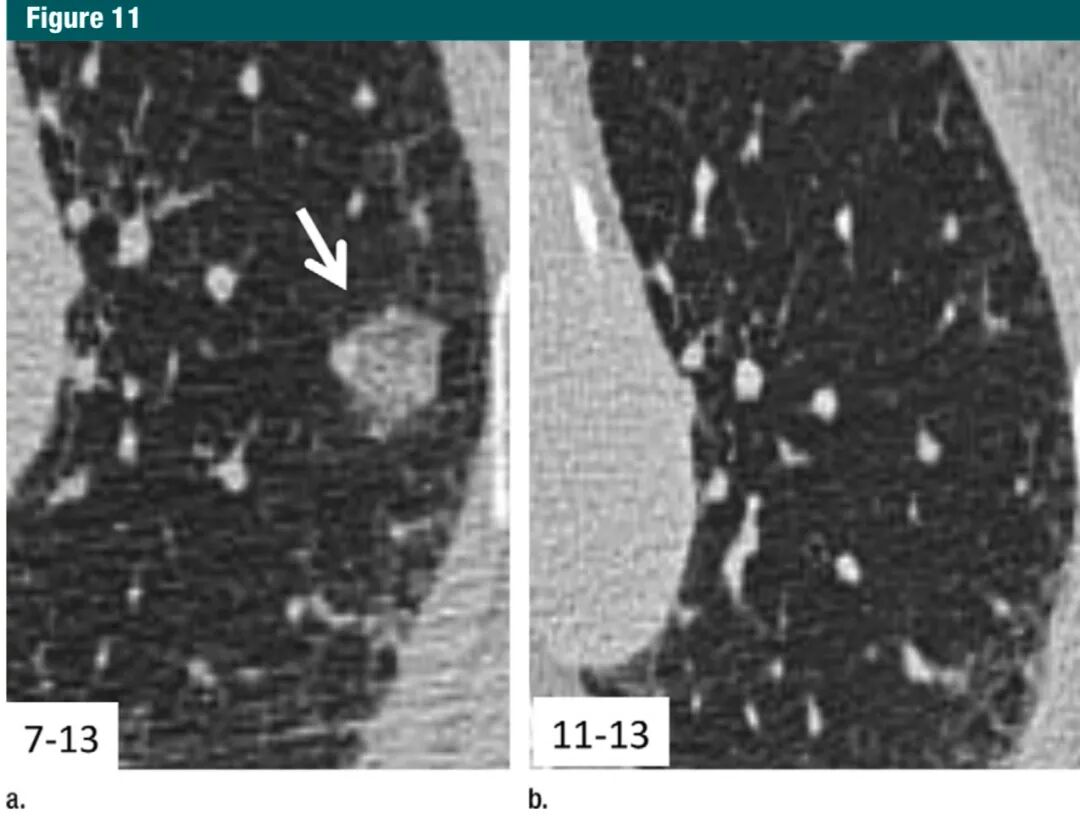

需特别注意有些患者对等待12月才随访CT感到不安,这种情况下,可以提前随访,因为这类病灶可能会被吸收或没有变化,能使患者得到安慰(图11)。再次强调,对独立个体来说,这些指南并不排斥更短或更长的随访,只要认为临床上合适。

图片7Gc帝国网站管理系统

图11:a. 横断面1mmCT层面,显示左肺上叶一个10mm磨玻璃结节(箭头);b.4个月后复查,图像显示未经治疗但病灶消失,符合良性病因,如局部感染